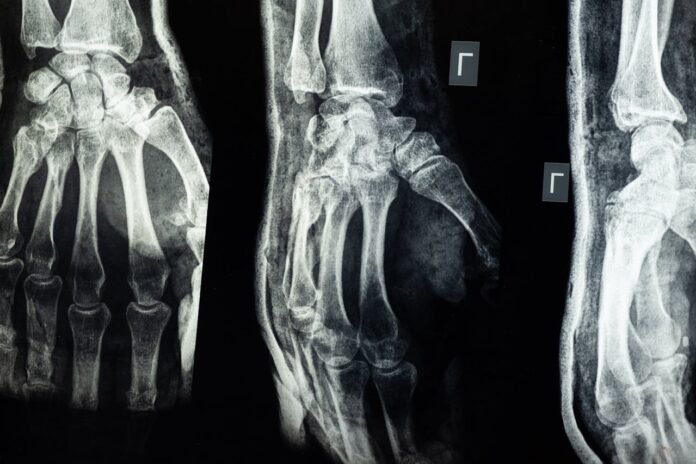

There are many different types of fractures. Some fractures, such as greenstick fractures, happen mostly in children, while others, such as compression fractures, are more common in adults. Each type of fracture has its own different type of management, including physiotherapy. Some of the common types of fractures are listed below:

- Closed fracture: As its name suggests, it is a fracture that is closed in nature. It does not pierce through the skin. Open fracture: In this type of fracture, there’s a broken bone that has pierced through the skin. It is more susceptible to infections.

- Oblique fracture: In this type of fracture, the bone is cracked at an angle, creating a line that runs diagonally around the bone.

- Comminuted fracture: This type of fracture happens when the bone is completely shattered into various pieces. This fracture often takes significantly longer to heal than other fractures.

- Greenstick fracture: This type of fracture is mostly common in children. There’s a small partial crack that doesn’t go all along. It is common in children because their bones are more flexible.

- Spiral fracture: This fracture happens when the bone is twisted and is broken due to the twisting motion. This fracture is mostly common in long bones. Hairline fracture: This type of fracture is more common in athletes. The fracture is due to too much activity placed on the bone, resulting in a small crack.